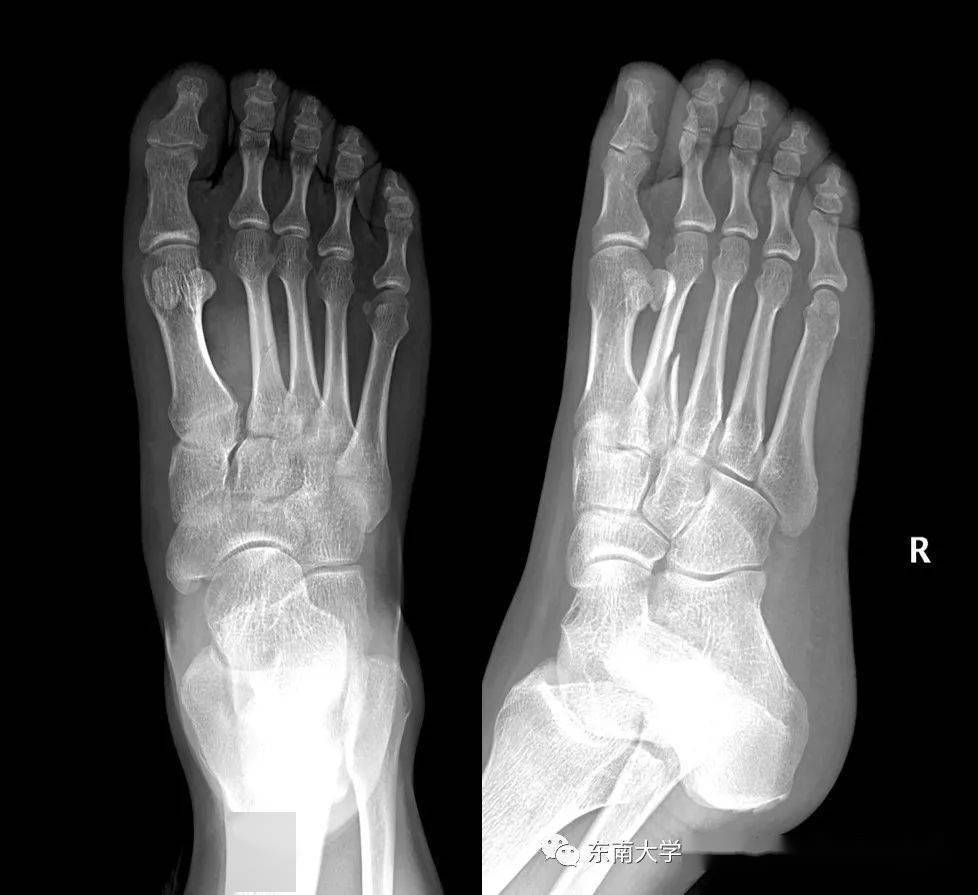

严重lisfranc损伤求治疗方案!

影像笔记:lisfranc损伤知识汇总